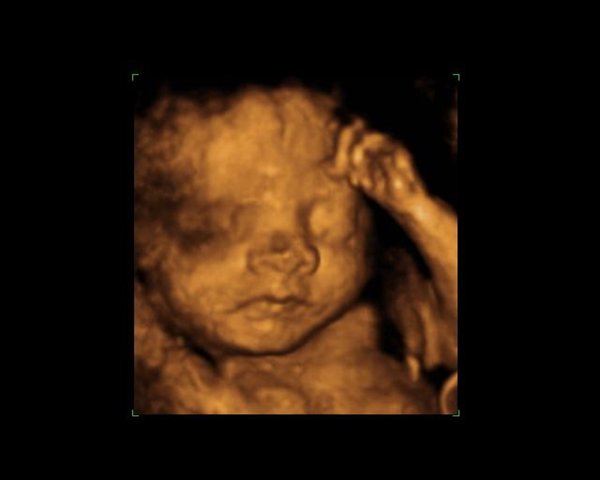

Jeg starter lige med Bianca.....

Jeg synes det meget hurtigt ses at det er Bianca og Celina, altså det kan ses allerede på de første billeder. Men også tydeligt at se hvor meget mindre de efterhånden ligner babyer